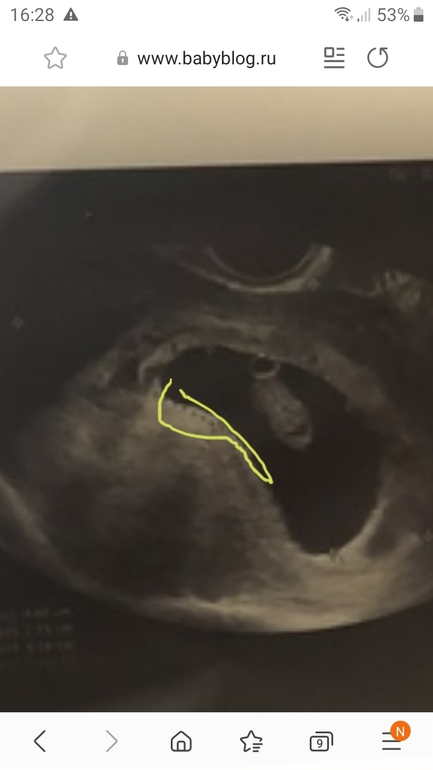

Я у вас не уверена где плацента, поэтому сложно сказать, первая мысль была мальчик, но когда стала смотреть именно плаценту, то засомневалась, если вы ее видите лучше, обведите ее иипришлите мне еще раз посмотреть

15.12.2020

Если бы я сама знала 😂😂😂😂 Может так лучше видно ? Вверху слева ножки